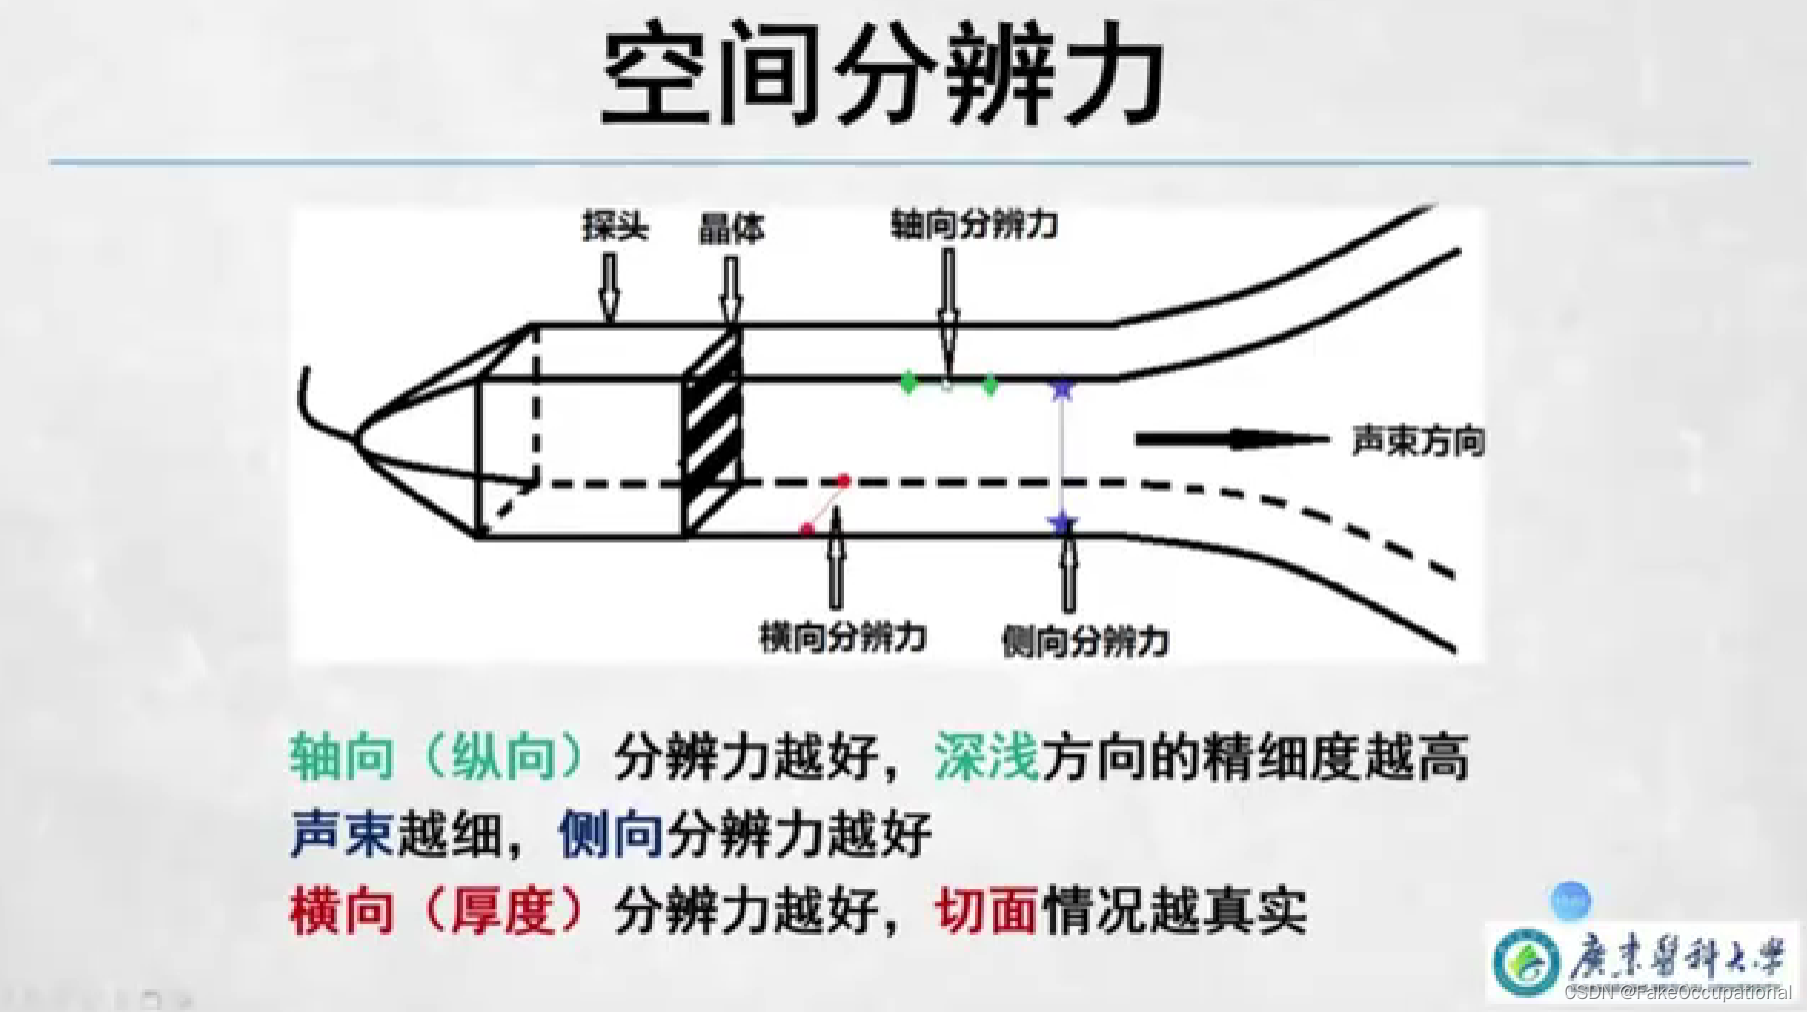

空间分辨力

- 显示屏上能够区分两个细小目标的能力

- 即两个目标的最小距离

- 分为轴向分辨力、横向分辨力和侧向分辨力